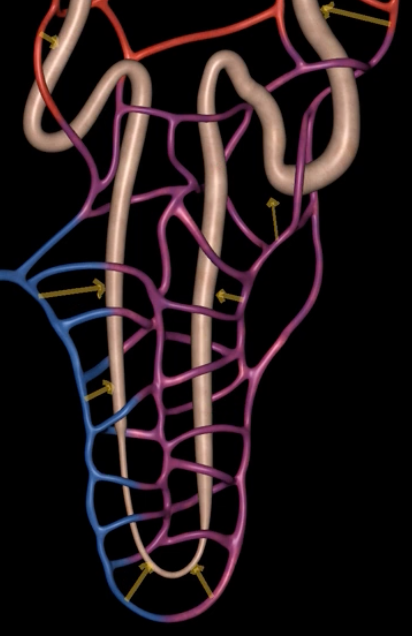

afferent arteriole

yellow

glomerulus

green

efferent arteriole

purple

orange: peritubular capillaries

green: vasa recta

efferent arteriole give rise to orange and green

yellow: cortical nephron

blue: juxtamedullary nephron

yellow:

blue: